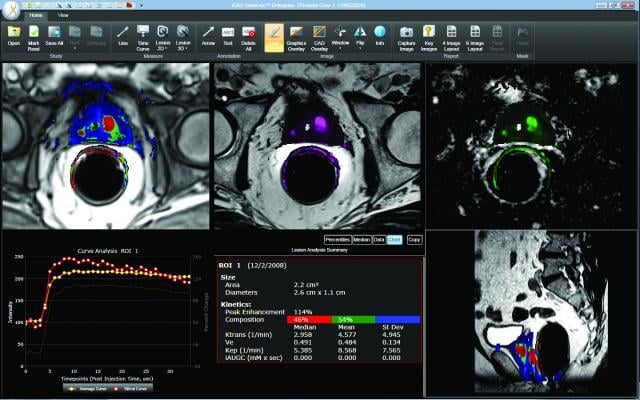

In the joint research project, the Netherlands Cancer Institute, University of Twente and industry partners Lightpoint Medical and Philips will evaluate a novel molecular imaging technology to image the prostate cancer biomarker prostate specific membrane antigen (PSMA) during surgery. If successful, the technology will be tested in larger clinical trials, with the aim of sparing healthy tissue and reducing recurrence rates in prostate cancer surgery.

Marcel Stokkel, M.D., nuclear medicine physician at NKI, commented, “If this technique is successful, we will be able to guide the urologist in the most optimal way by combining pre-operative staging with per-operative imaging using the same tracer. If the resection margins can be assessed with highest accuracy during surgery, we might become able to improve recurrence and survival rates. The collaboration with Lightpoint Medical, Philips and the University of Twente is the most optimal setting to reach this goal and to complete this study.”